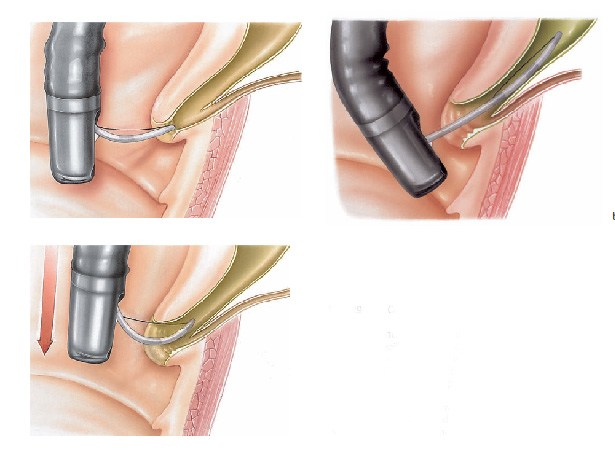

- Dilatadores flexíveis: uma série de sondas graduadas (espessura crescente) chamadas de sondas termoplásticas podem ser usadas. Estes são tubos que passam através do esófago para o estômago. Os tubos utilizados tornam-se progressivamente maior, até que o tamanho desejado seja atingido

- Balões dilatadores: a dilatação do esôfago pode ser feita usando balões durante a endoscopia. A endoscopia flexível permite ao examinador visualizar diretamente a estenose. Um balão é introduzido pelo canal do aparelho até a zona de estreitamento. Ele é então insuflado com água até uma certa pressão, que é pré-ajustada para uma dada circunferência. Quando insuflado, torna-se em forma de salsicha, esticado, e faz com que a estenose se abra.

Tratamento da Acalasia

- A Acalasia requer um tipo de balão específico, mais longo e maior, chamado de balão pneumático. Nesta situação, as fibras musculares espásticas na parte inferior do esôfago são esticadas.

Estenoplastia

Em algumas ocasiões, o estreitamento (estenose) é tão grande que nem os instrumentos de dilatação conseguem passar. Nestes casos e em algumas outras situações, realiza-se o procedimento de estenoplastia. Este consiste na realização de pequenos cortes na região da estenose com auxílio de um estilete que é passado pelo canal de trabalho do endoscópio. Estes pequenos cortes ajudam abrir o estreitamento facilitando a passagem dos dilatadores e acelerando o processo do tratamento. Em alguns casos após a realização dos pequenos cortes algumas substâncias, como corticóides, são injetadas na região para prevenir que o estreitamento feche novamente com facilidade.